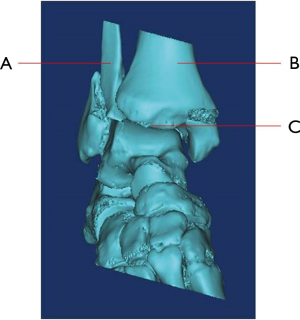

1. What’s name of bone that marked as “A”

- Ulna

- Radius

- Fibula

- Tibia

2. What’s name of bone that marked as “B”

- Ulna

- Radius

- Fibula

- Tibia

3. Which bone involves fracture?

- None of “A” and “B”

- Both of “A” and “B”

- Only “A”

- Only “B”

4. What’s name of the joint that marked as “C”?

- Knee Joint

- Elbow joint

- Ankle joint

- Wrist joint

5. What’s the name of bone that locates at distal end of “A” and “B”?

- Calcaneus

- Talus

- Cuboid bone

- Navicular bone